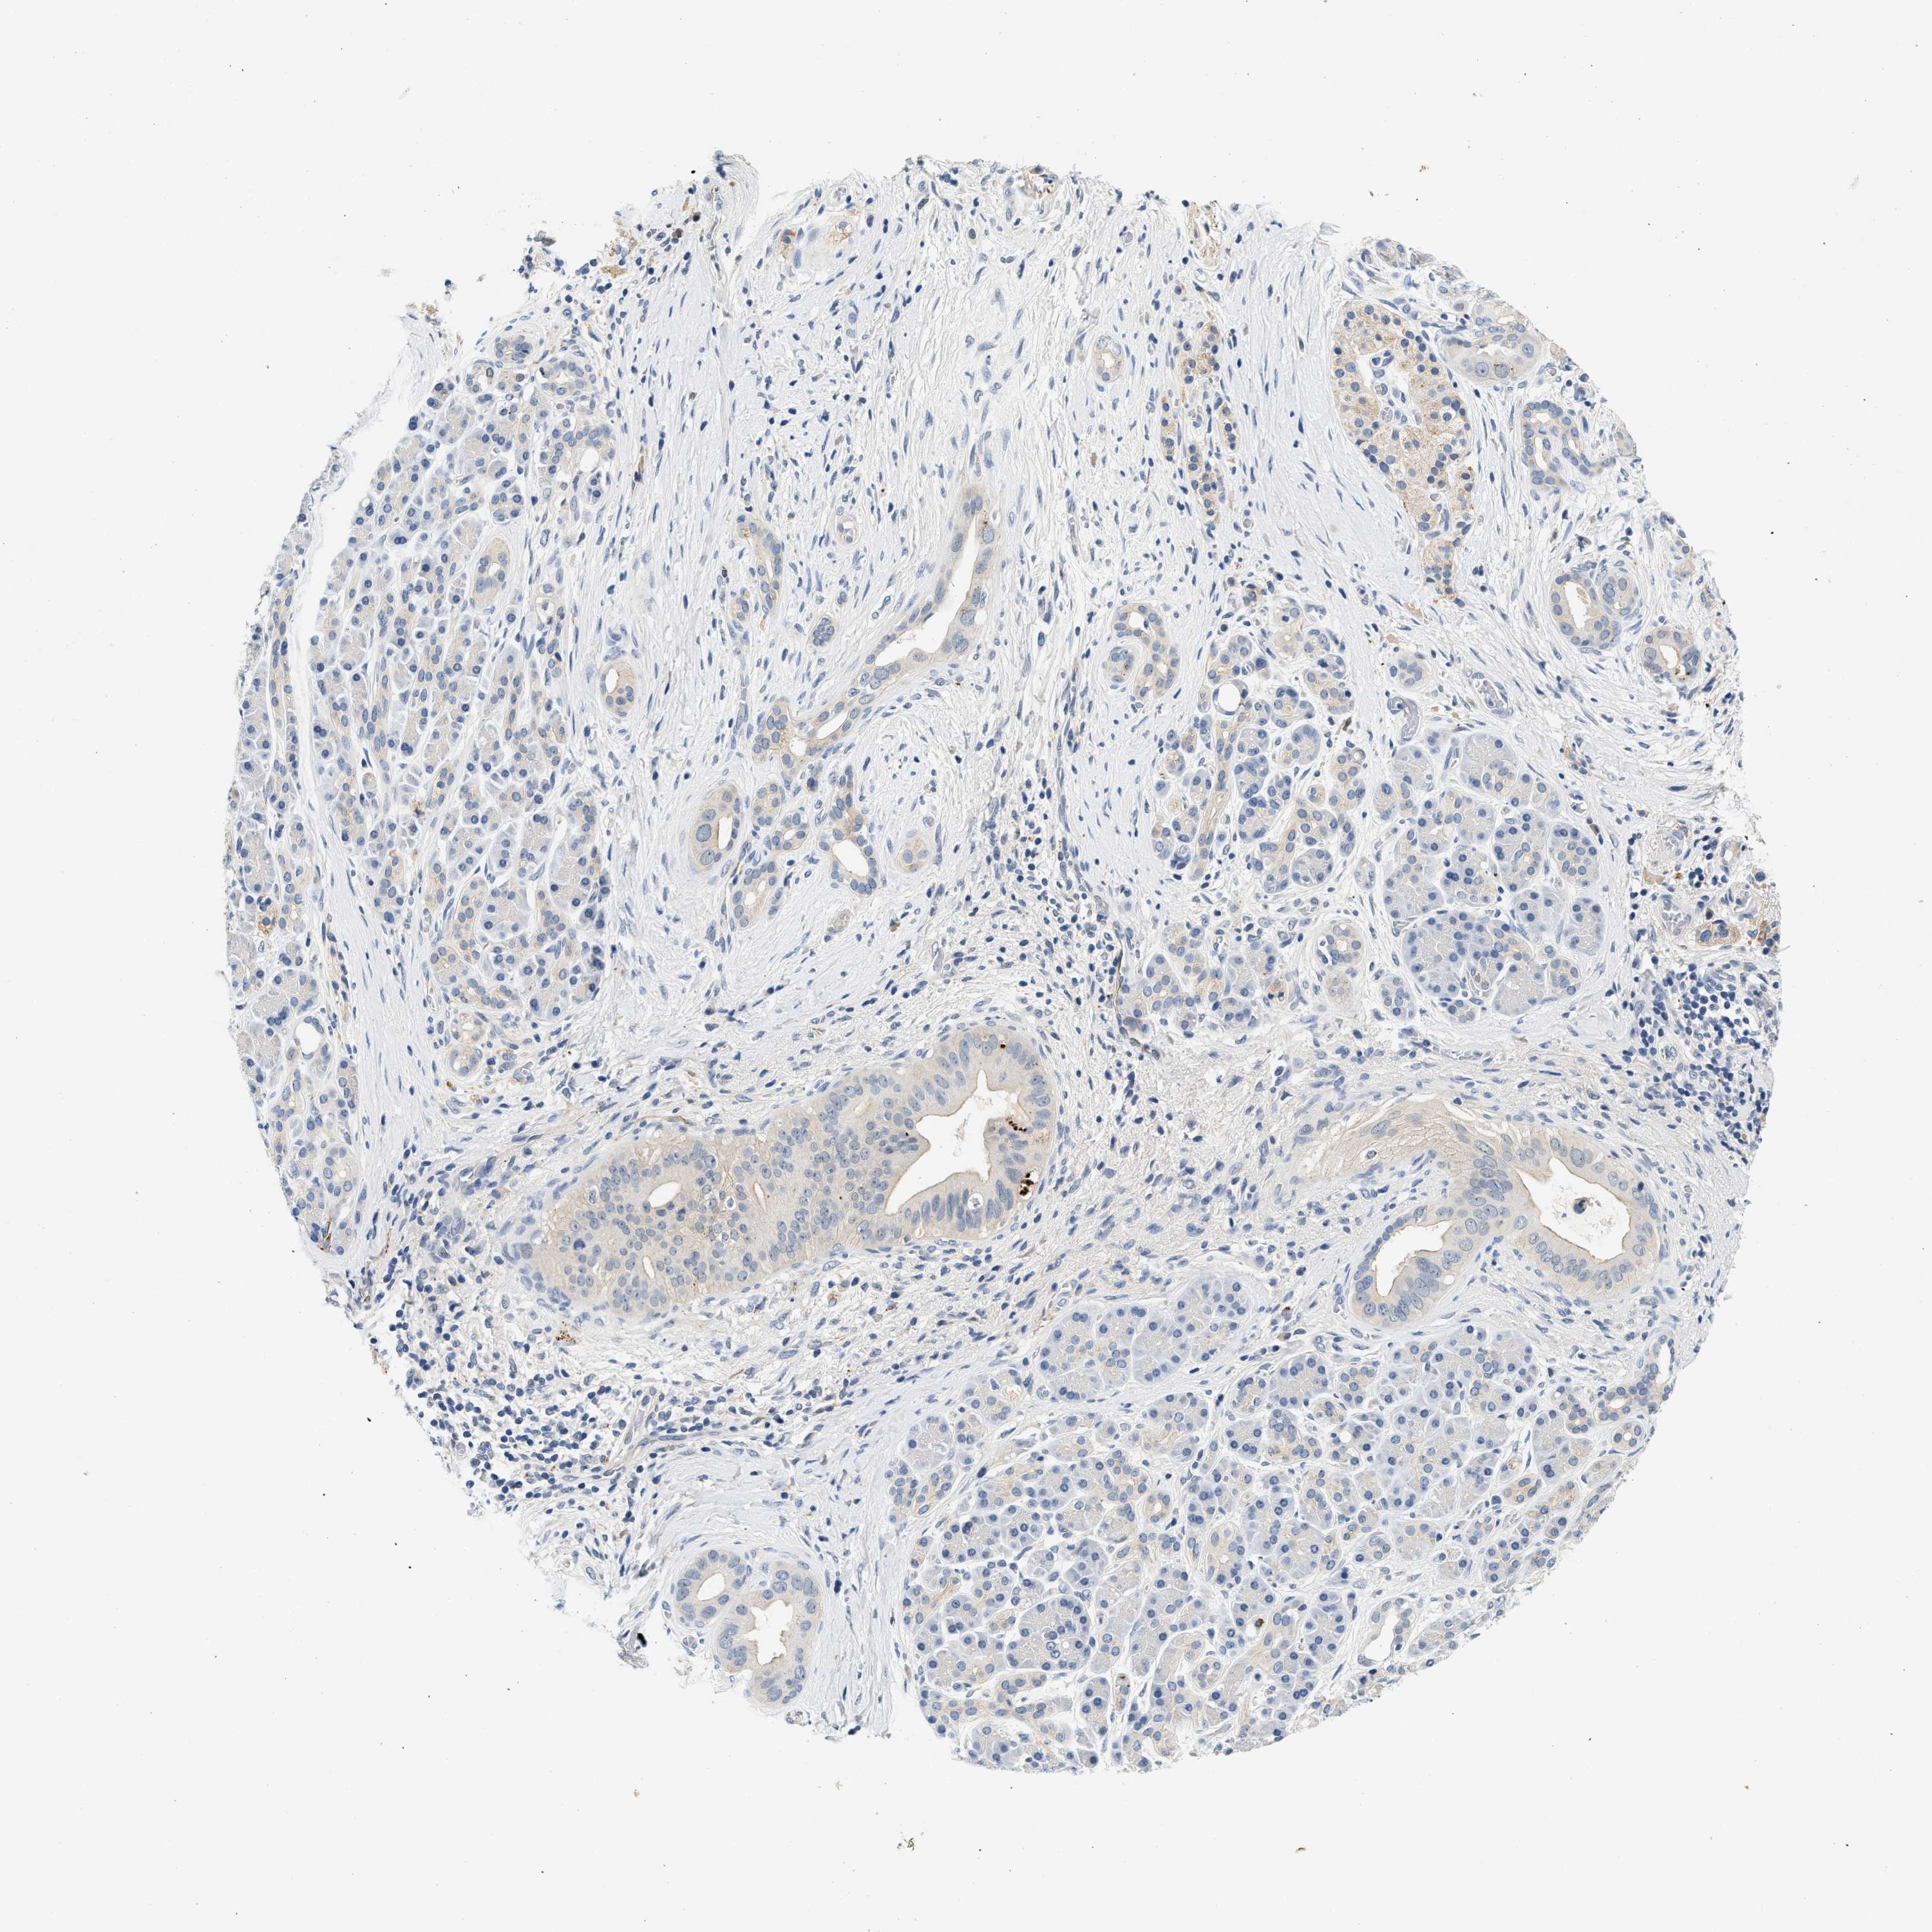

PANCREATIC CANCER - Protein expressioni

A mouse-over function shows sample information and annotation data. Click on an image to view it in a full screen mode. Samples can be filtered based on level of antibody staining by selecting one or several of the following categories: high, medium, low and not detected. The assay and annotation is described here.

Note that samples used for immunohistochemistry by the Human Protein Atlas do not correspond to samples in the TCGA dataset.

Antibody stainingi

Antibody staining in the annotated cell types in the current human tissue is reported as not detected, low, medium, or high, based on conventional immunohistochemistry profiling in selected tissues. This score is based on the combination of the staining intensity and fraction of stained cells.

Each image is clickable and will lead to virtual microscopy that enables deeper exploration of all samples and also displays staining intensity scores, fraction scores and subcellular localization as well as patient and tissue information for each sample.

Antibody HPA020391

Staining

High

Medium

Low

Not detected

Intensity

Strong

Moderate

Weak

Negative

Quantity

>75%

75%-25%

<25%

None

Location

Nuclear

Cytoplasmic/membranous

Cytoplasmic/membranous,nuclear

Adenocarcinoma, NOS